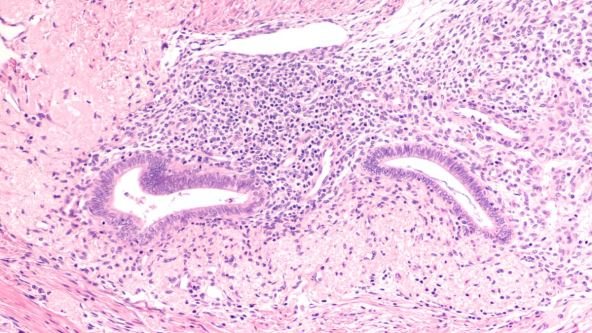

Endometrioza ispod mikroskopa

Foto: Shutterstock